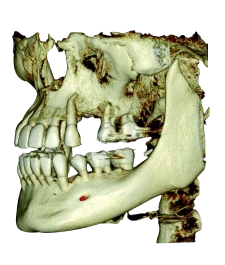

Ещё больше применений в стоматологии

- Ортодонтия

- Всё на Х-имплантах

- Ортогнатическая хирургия

- Реконструкция лица

- Травмы

- Анализ пазух и дыхательных путей

- Эндодонтия

- Имплантология

- Двойной ВНЧС

- Скученность зубов

С помощью RAYSCAN приоритетное внимание уделяется индивидуальности каждого пациента, предлагая настраиваемые объёмы сканирования и изображения с высоким разрешением. Это гарантирует получение чётких диагностических изображений, позволяет ставить верные диагнозы и целенаправленно планировать лечение.